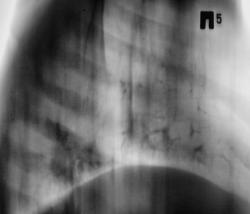

У пациента диагностирована полисегментарная нижнедолевая пневмония. Проведено противовоспалительное лечение "по схеме". Наступило клиническое выздоровление, пациент чувствует себя хорошо. Аускультативно - "норма". Пациент готовится к выписке.

Проведена рентгенография в прямой и правой боковой проекциях.

Возникло обоснованное сомнение в "полном клиническом выздоровлении". Решено сделать томографию в боковой проекции.